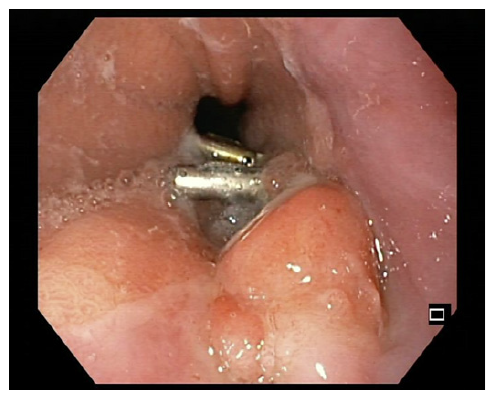

One week before the scheduled endoscopy, the patient once again presented at the ED, experiencing a recurrence of melena for 2 days and a blood count showing a hemoglobin of 11.6 g/dL. Subsequent endoscopy unveiled a distinctive 15 mm nodular subepithelial lesion at the gastroesophageal junction, with ulceration and a visible vessel at the proximal margin of the gastric mucosa. It was treated with 4 mL of diluted adrenaline injection and a clip placement on the vessel (shown in Fig. 2). An endoscopic ultrasound (EUS) revealed a homogeneous and hypoechoic lesion measuring 15 × 6 mm with well-defined limits at the deep mucosa (shown in Fig. 3). No local suspicious lymph nodes were observed. Histological examination of the biopsies of the lesion confirmed the presence of an adenocarcinoma. Subsequent computed tomography scans of the chest and abdomen revealed that the lesion retained clear cleavage plans with the surrounding structures, without suspicious adenopathies in its vicinity. After staging, the patient decided to change the health institution, which led to a month-long delay in treatment. Following a comprehensive multidisciplinary discussion, it was decided to proceed with a surgical approach, namely a distal esophagectomy and total gastrectomy.

Fig. 2 15-mm nodular subepithelial lesion at the gastroesophageal junction with ulceration in the proximal margin of the gastric mucosa.